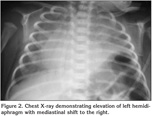

On the 26th day chest tube was replaced depending on the attempts to wean the patient from the ventilator were unsuccessful. He appeared distressed and hypoxic even on continuous positive airway pressure. On physical examination breath sounds were absent over the lower half of the left chest. Chest X-ray showed elevation of the left hemidiaphragm and ultrasonography of the diaphragm demonstrated absent movement during spontaneous breathing (Figure 2). The infant underwent to thoracotomy and plication of the left hemidiaphragm. He was successfully extubated on the second postoperative day. After three days of nasal continuous positive airways pressure, he subsequently required only 25% of supplementary oxygen. A chest X-ray 3 weeks later showed reexpansion of the left lung with normal diaphragmatic position (Figure 3). He was eventually discharged to home at 38 days of age.

Figure 3